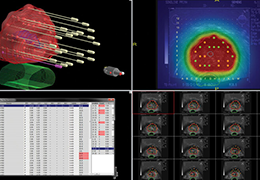

Data Analysis

Data Analysis

Data analysis includes preprocessing, correlation analysis, determination of Talairach coordinates, volume rendering, surface rendering and cortex flattening.

Preprocessing

Preprocessing includes motion correction, Gaussian spatial and temporal data smoothing, linear trend removal and filtering in the frequency domain.

Statistical Analysis

BrainVoyager performs a wide range of statistical analyses including; parametrical mapping, contribution maps, Independent Component Analysis (ICA), Region-of-interest analysis and Event-related fMRI analysis. specifications.

Analysis tools, modules and plugins

ANCOVA module: allows import and analyses of multi-subject data sets.

Self-Organizing Group ICA Plugin: allows group level ICA by analyzing the spatial similarity of independent components across subjects.

Group Data Simulator Plugin: creates multi-subject data sets allowing to test new analysis tools as well as to learn how to analyze planned fMRI experiments.

Fuzzy Clustering of Time Courses Plugin: allows clustering voxels of VTC data sets with respect to the similarity of their time courses.

Group-level cortical thickness analysis (CTA): can now be performed using cortically aligned brains.

Granger Causality Mapping: to estimate influences between brain areas

Multiple Comparison Correction: using a cluster-size threshold

BOLD Latency Mapping